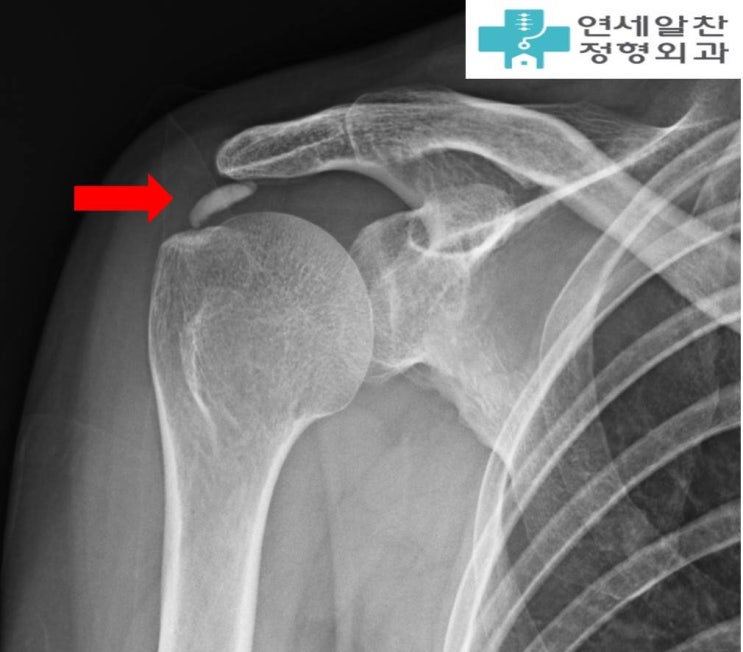

어깨 석회, 주사치료 vs 충격파 vs 석회분쇄흡입술 비교

안녕하세요. 정형외과 전문의 이동규원장 입니다. "석회성건염이라는데, 주사 맞으면 되나요?" &...